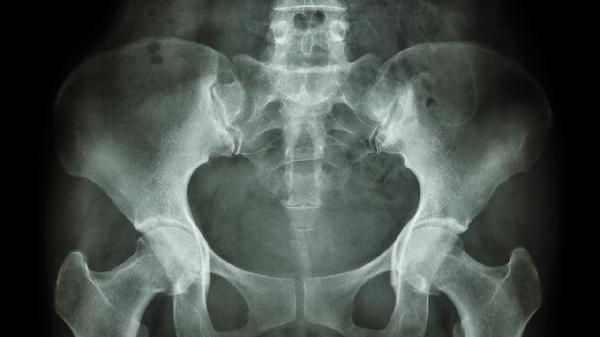

治疗坐骨神经痛的药物主要有甲钴胺片、塞来昔布胶囊、双氯芬酸钠缓释片、加巴喷丁胶囊、普瑞巴林胶囊等。坐骨神经痛可能与腰椎间盘突出、梨状肌综合征等因素有关,通常表现为臀部至下肢放射性疼痛、麻木等症状。建议及时就医,在医生指导下规范用药。